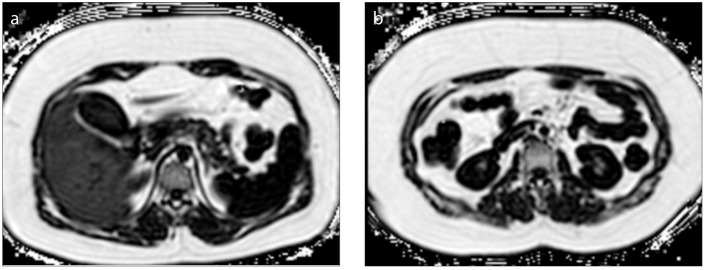

Magnetic resonance imaging-proton density fat fraction (MRI-PDFF) is an emerging quantitative imaging biomarker that accurately measures the fat fraction of tissue by correcting factors influencing magnetic resonance signal intensity. Beyond fat quantification, it also measures R2* which is a direct measure of iron concentration. The utilization of MRI-PDFF in liver diseases is well established. In the present review, we focused on applications of MRI-PDFF in different body areas including pancreas, bone, muscle, spleen, testis, visceral, and subcutaneous adipose tissue. Future studies can enable tracking of quantitative fat fraction changes in different organs simultaneously, which can be critical in understanding fat metabolism.